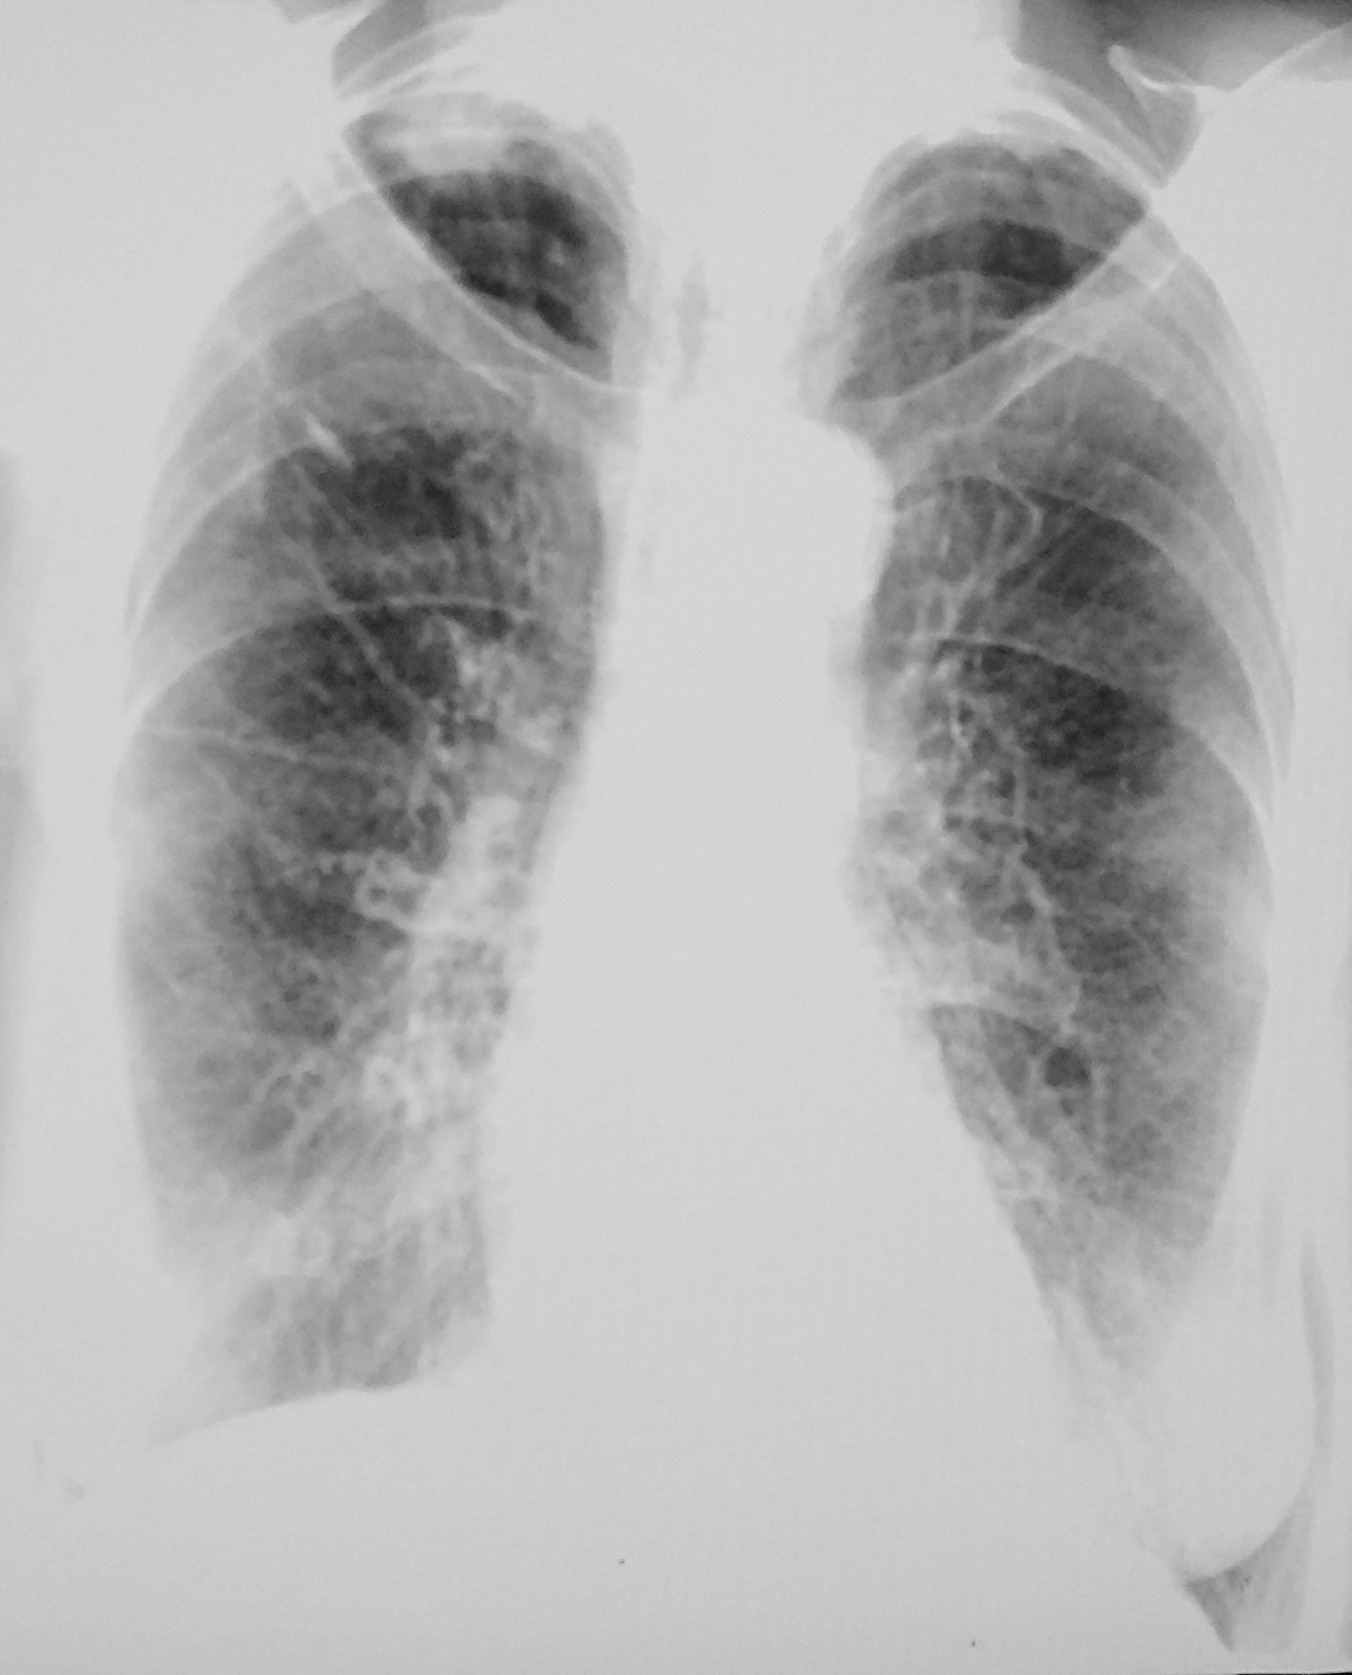

Рентгеновские снимки опухоли Панкоста